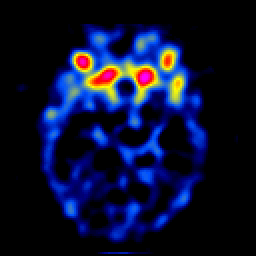

SPECT TL Study #4 -- Slice #21